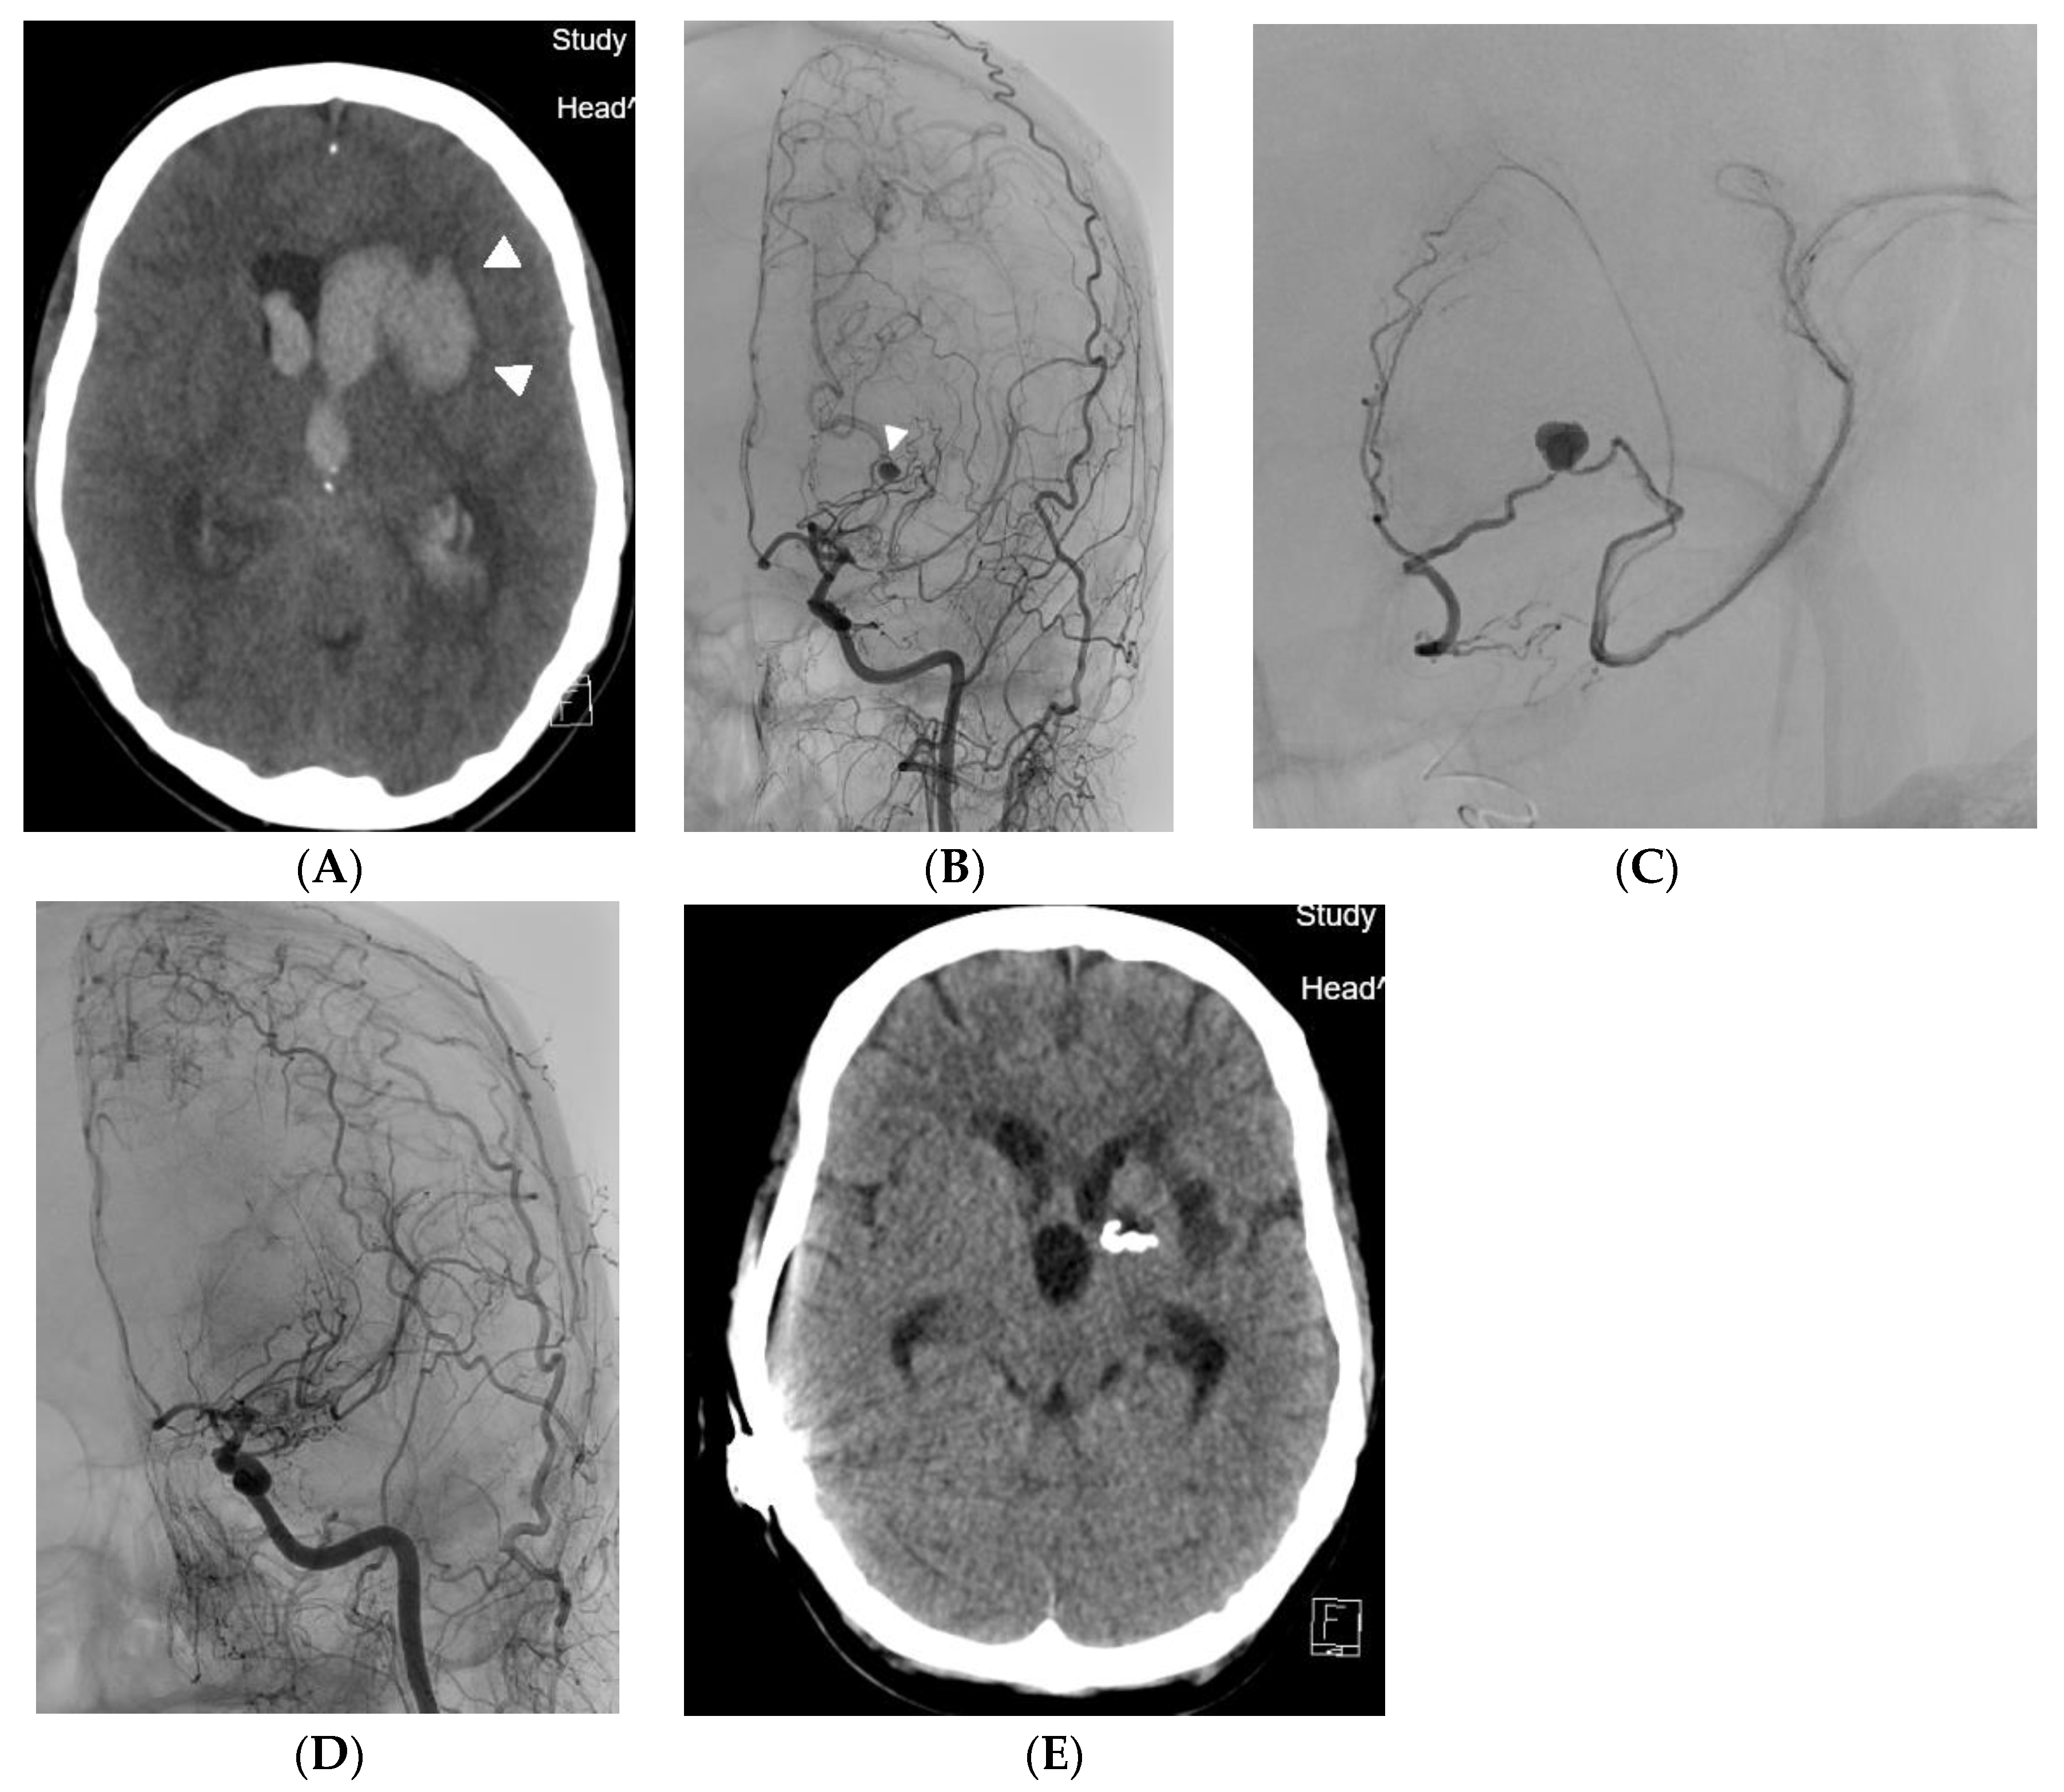

A 47-year-old woman was admitted for a sudden onset of severe headache, CT scan showed four-ventricle hematocephalus. CTA showed a spot sign in the left lateral ventricle (Figure 2A). The patient was taken to the angiography suite and placed under general endotracheal anesthesia. A 4 mm aneurysm on the collateral vessel–anterior choroidal artery bridging the closure of the terminal segment of the internal carotid artery was diagnosed as the source of bleeding (Figure 2B). Selective catheterization of the anterior chorioidal artery using the 1.2F Magic microcatheter with 0.007 microwire, and distal embolisation with acrylic glue mixed with Lipiodol in a ratio 1:9 was done (Figure 2C). Since glue cast has not been seen on fluoroscopy and DSA, flat panel CT was used to verify penetration of glue mixture into the aneurysm (Figure 2D). After embolisation, the patient received a ventricular drainage for massive hematocephalus. The patient is without deficit and works as a teacher. The patient had a follow-up DSA two months after embolisation, which confirmed closure of the embolised aneurysm and excluded new ones. Five months later, an unsuccessful attempt was made to perform EC-IC bypass to prevent the development of another aneurysm [8]. The patient is uneventful and has been genetically proven to have MMD, which was already confirmed in her daughter before the bleeding occurred.

Figure 2. (A) Case 2. CT angiogram showing an aneurysm (arrowhead) in the left lateral ventricle on moyamoya collateral, which was cause of hematocephalus. (B) Case 2. Three dimentional angiogram showing the hypertrophic anterior chorioidal artery (pair of arrows) as collateral bridging the left internal carotid artery intracranially. The contralateral arrow indicates the aneurysm seen on the CT angiogram. (C) Case 2. According to the 3D angiogram, the microcatheter was navigated through the anterior chorioidal artery to the vicinity of the aneurysm. The blood flow in the artery is slowed, so the aneurysm fills only partially and the contrast agent forms a level (arrow). (D) Case 2. Angiogram after acrylic and oily contrast mixture injection shows that the target aneurysm is no longer filling, as well as on control angiography 2 months later. (E) Case 2. Flat panel CT demonstrates embolic mixture penetration into the embolised aneurysm, which was not visible during injection of the embolising agent or on angiography immediately after embolisation. Symmetric calcifications within the lateral ventricles are in the chorioid plexus.